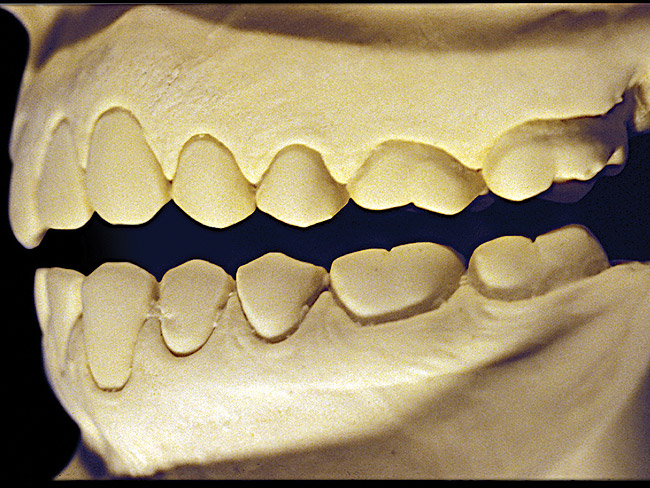

The patient shown in Figure 3 and Figure 4 exhibited severe NCLTS from bruxism. Examination of the casts indicated that the NCLTS was progressively greater toward the anterior teeth. Cupping and cratering was not present because there was no secondary cause. Figure 5 and Figure 6 detail another bruxism patient, but to a lesser degree and one with cupping/cratering caused by toothpaste. The cups or craters were not caused from bruxism because the teeth could not touch the bottom of the invaginations. In both featured patients, upon hand-articulating the casts, the NCLTS facets matched up and the diagnosis of bruxism was confirmed.

Figure 5  Moderate NCLTS from bruxism, maxillary arch.

Figure 5